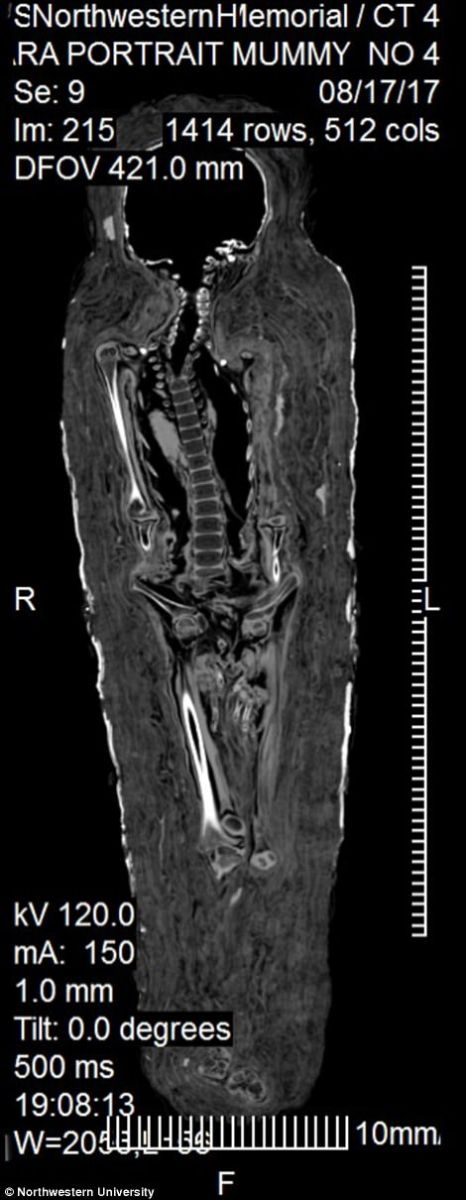

Двохтисячорічна мумія унікальна тим, що збереглася нерозкритою з моменту виявлення. Вчені відзначають, що мумії такого роду, з портретом померлого, практично не дійшли до наших днів. Щоб зберегти унікальний артефакт, його досліджували за допомогою рентгеноскопії.

Як показали дослідження, єгипетській дівчинці на момент смерті було близько 5 років — її зріст становив близько 0,9 м, а кістки і зуби відповідають саме цьому віку.

У тіла немає видимих пошкоджень, з чого зробили висновок, що дитина померла від хвороби.